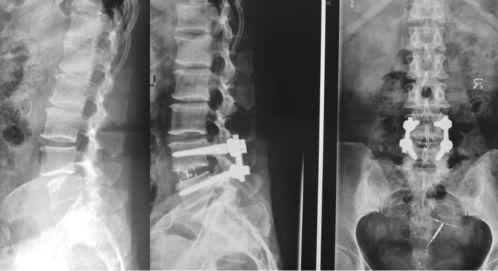

首先,我们来揭开腰椎突出的神秘面纱。腰椎突出,顾名思义,就是腰椎间盘的一部分从正常位置突出,压迫到周围的神经根,导致一系列不适症状。据统计,我国腰椎突出患者人数已超过1亿,而且这个数字还在逐年攀升。

三、腰椎突出的症状

腰椎突出有哪些症状呢?以下是一些常见的表现:

1. 腰痛:这是腰椎突出的最常见症状,疼痛可能局限于腰部,也可能向下放射至臀部、大腿后侧。

2. 下肢疼痛、麻木:当突出的椎间盘压迫到神经根时,会引起下肢疼痛、麻木,甚至无力。

3. 活动受限:腰椎突出可能导致腰部活动受限,比如弯腰、转身等动作变得困难。